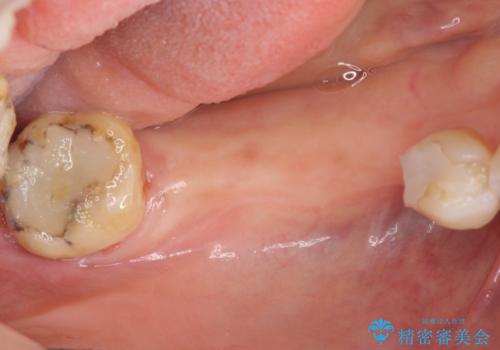

失った奥歯をインプラントで機能回復

- 3本失った奥歯の機能回復するために、インプラント治療を希望され来院されました。

インプラント以外にとりうる機能回復の代替手段は「入れ歯」、となります。

よりしっかりと噛むことのできるインプラントによる治療を進めていくこととなりました。